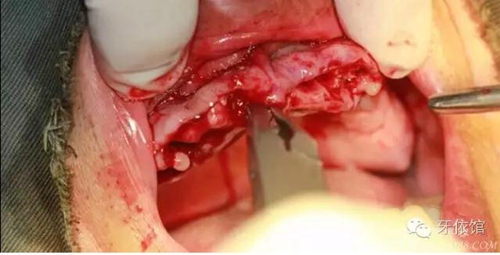

去除多余軟組織

將攜帶體重新與植體連接

將左側(cè)5(5個月前種的)連接轉(zhuǎn)移桿

縫合

取模型

安置愈合基臺

第二天患者來帶臨時冠口內(nèi)情況,患者沒有絲毫腫脹

戴入臨時冠

的確,切牙孔神經(jīng)破壞后患者口內(nèi)感覺似乎沒有任何異樣,當(dāng)然此患者較易滿足,我不排除如果遇上一個心思縝密個患者,是否他也會這樣感覺沒有變化。